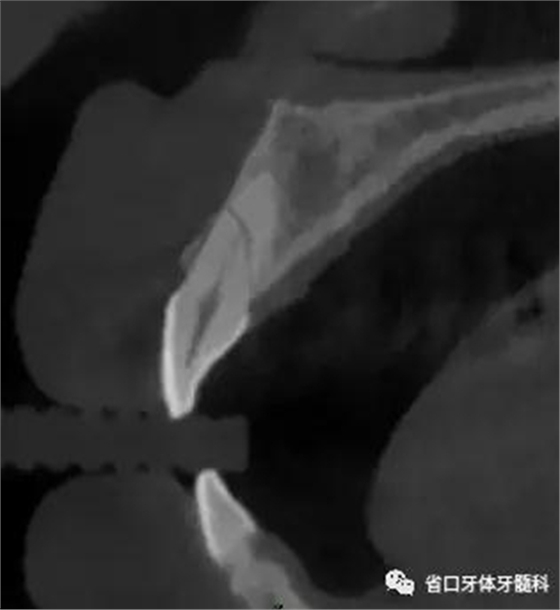

CBCT:11、21頸部以下均見一完全性折裂線,兩牙折裂線均位于頜骨內(nèi)且斷端移位不明顯,相應(yīng)唇側(cè)骨板亦見斷裂且輕度移位。

圖3:11術(shù)前CT